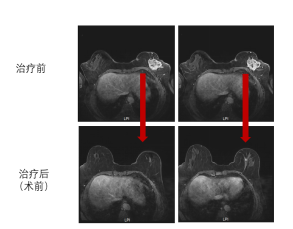

乳房肿块治疗后基本消失

淋巴结退缩至正常范围